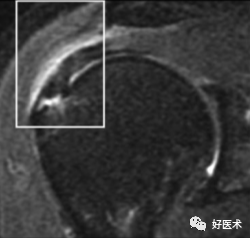

3)完全性撕裂

原发征象:肌腱局部缺如,连续性液体信号横贯肌腱的全层,这使得盂肱关节和肩峰下滑囊相通。

继发征象:

①肩峰下滑膜囊积液,积液在T1WI /PDWI上呈中等信号,T2WI+FS上呈高信号;

②冈上肌肌肉、肌腱结合处回缩(正常位置在肱骨头上方);

③滑囊旁脂肪垫的渗出丢失。

MR 关节造影:局限性或弥漫性充满造影剂的裂隙贯穿肌腱全层,肌腱失去其连续性。